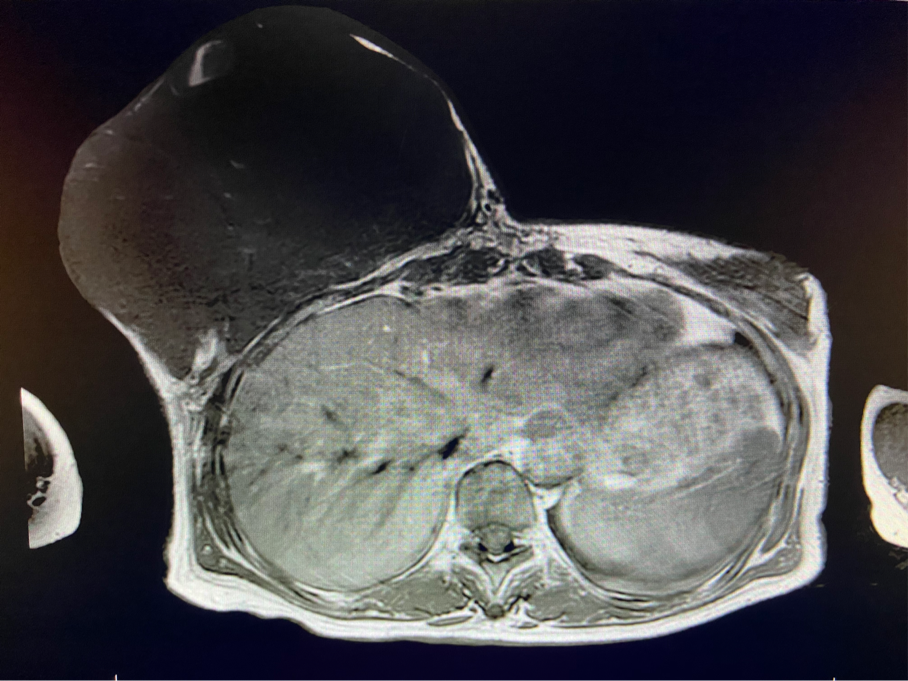

2周前,王女士的右乳外下方皮膚破潰,伴大量滲液,還發(fā)出陣陣惡臭。經(jīng)多方打聽,王女士從外地來到西安國際醫(yī)學(xué)中心醫(yī)院甲乳外科劉曉敏主任處就診。入院后,迅速完善了一系列相關(guān)術(shù)前檢查:王女士的雙乳外形不對(duì)稱,右乳約22?20cm,皮膚水腫明顯并可見靜脈曲張。右乳外下象限皮膚可見局部破潰,創(chuàng)面有3處,共約6?4cm大小,創(chuàng)面呈暗紅色,伴有血性滲出及惡臭,局部皮膚溫度升高。右側(cè)腋窩可觸及腫大淋巴結(jié)。

該患者右乳巨大腫物術(shù)前初步考慮乳腺葉狀腫瘤可能,因腫瘤太大,幾乎遍及整個(gè)右側(cè)乳房,為保證“無瘤原則”,術(shù)中切除范圍位置未知,極有可能出現(xiàn)皮瓣缺損。于是,經(jīng)過和整形醫(yī)院郭樹忠院長(zhǎng)、整形外科王愛武主任的討論,提供了兩種手術(shù)方式,一是創(chuàng)面修復(fù)(植皮或轉(zhuǎn)移皮瓣修復(fù)創(chuàng)面),二是乳房再造,與患者及家屬溝通后,決定先解決腫物,3年病情不再復(fù)發(fā)后,可以再考慮乳房重建。